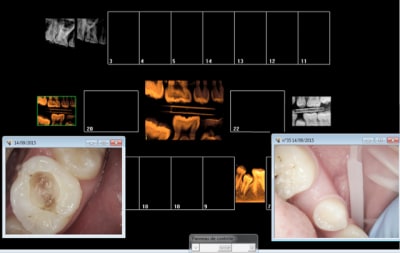

Celles là ?

Justification rétro alvéolaires :

Carie pénétrante 16, Absence injustifiée 35.